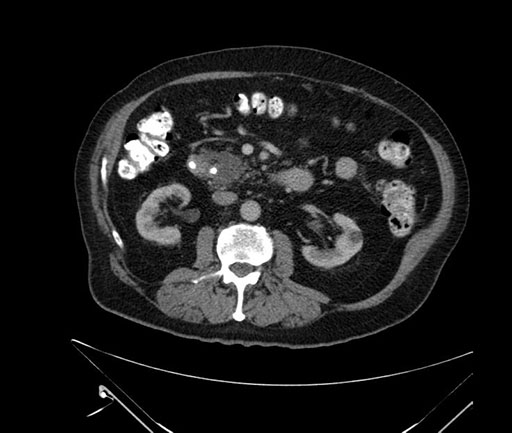

Axial - stented